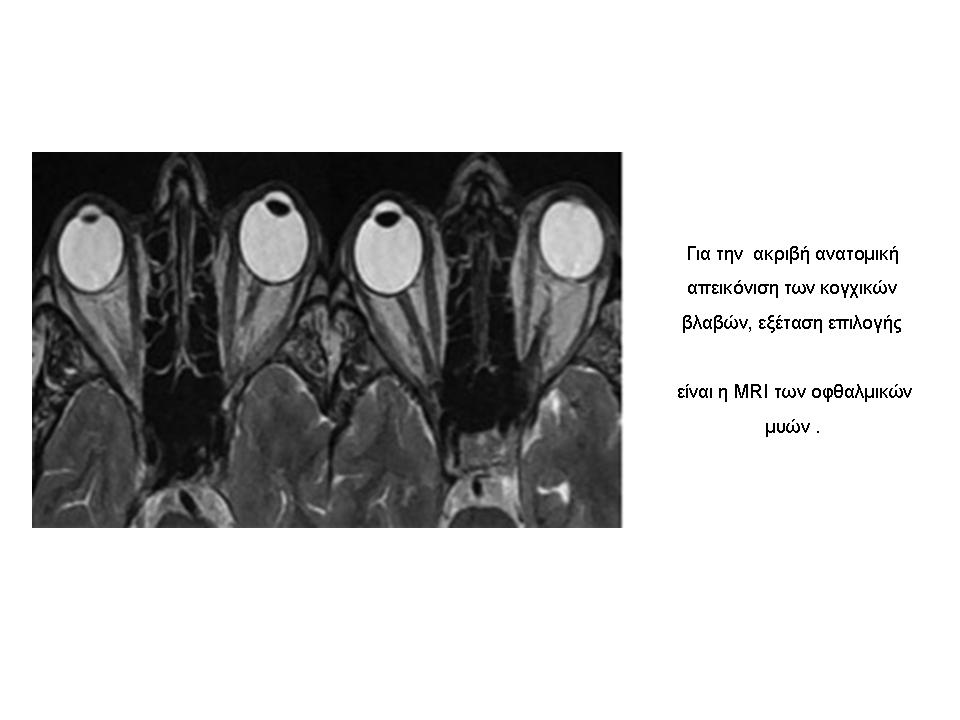

- Η μαγνητική τομογραφία (MRI) των οφθαλμικών μυών.